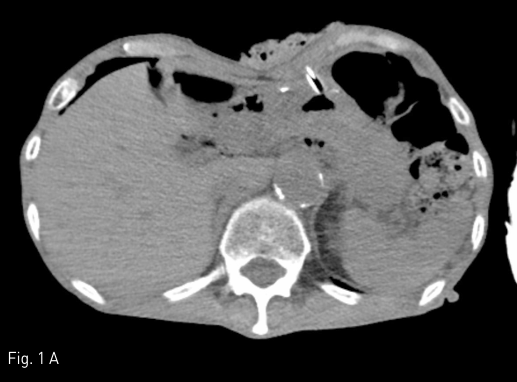

Fig 2A

Left internal mammary arteriography was performed after selection with 5-Fr angiographic catheter and microcatheter system, which revealed active contrast extravasation from a branch of superior epigastric artery (A, arrowhead).